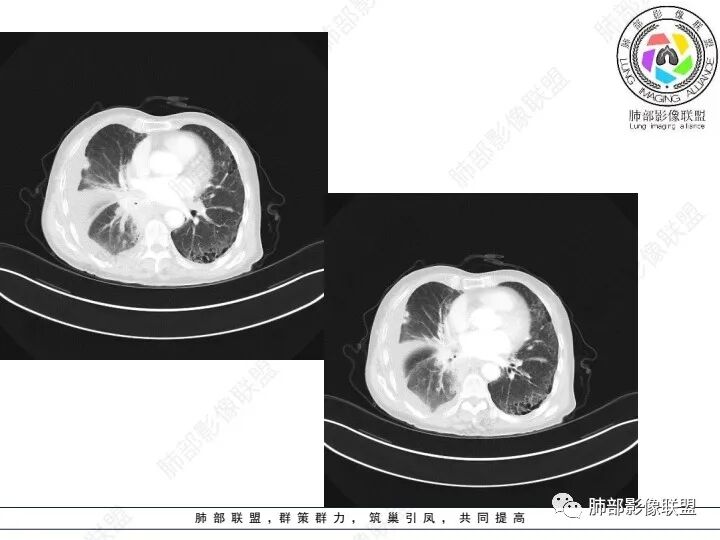

精彩讨论

右肺下叶胸膜下不规则肿块,与肺门相连,不均匀强化,胸壁受侵,右肺内多发小结节,下叶血管束增粗,小叶间隔增厚,右肺门及纵膈多发淋肿大淋巴结,融合,右侧胸水,考虑腺癌转移

患者老年女性,腹痛、黑便4小时。查肿瘤结果CA125明显升高,余正常。胸部CT:双肺胸膜下间质性改变,右肺胸膜下多发结节灶,以右肺下叶为大,增强渐进性强化,内低密度灶。右肺门淋巴结肿大伴钙化,右中间支气管狭窄,右侧包裹性胸腔积液。综合考虑恶性,腺癌可能大。鉴别转移。

肺门肿块环形包绕气管,右肺下叶可见一环状强化肿块,右侧胸膜多发强化结节,首先考虑结核并结核性胸膜炎

右肺下叶胸膜下肿块,密度不均,不均匀强化,胸膜栽赃,右肺多发小结节,右肺门及纵膈多发淋肿大淋巴结,下叶支气管受压变窄,右侧胸水,考虑恶性,腺癌转移。

右肺下叶占位,右肺下叶支气管狭窄,周围见软组织密度结节包饶,增强结节病灶强化不明显,右肺胸膜下见多个结节影,考虑恶性病变,低分化腺癌可能

老年女性,以消化道出血入院,右肺下叶靠近脊柱旁肿块,边缘毛糙,有栽赃,内有坏死,胸膜多发结节,右侧胸腔积液,同侧肺门纵隔多发肿大淋巴结,考虑恶性肿瘤可能,不知是一元还是二元,一元消化道肿瘤肺转移?或者二元肺部肿瘤胸膜转移,肿瘤标志物不是很高,考虑间皮瘤?淋巴瘤?

老年女性,右肺门增大见软组织密度影,包绕右肺主支气管腔,管腔明显变窄,并阻塞性肺炎,右侧胸腔及叶间积液,考虑恶性,小 细胞肺癌可能大,鉴别结核

右下肺实变影,周围模糊,均匀强化,内可见低密度坏死,局部胸膜肥厚粘连,胸腔积液,纵隔淋巴结肿大,恶性肿瘤要首先排除。

老年女性,肺气肿背景。腹痛、便血入院。右肺下叶脊柱旁软组织肿块,强化不均匀,中心有坏死,纵隔及双侧肺门多发肿大淋巴结、有融合,右下支气管周围为主,包绕支气管生长,且管壁增厚伴环形钙化、狭窄,增强后有环形强化。右侧胸膜见结节灶,增强后明显强化;右侧胸腔积液。考虑:右下肺恶性肿瘤伴纵隔、肺门多发肿大淋巴结,胸膜转移,低分化腺癌?Ca125明显升高,老年女性 是否有妇科恶性肿瘤?黏液腺癌 肺内、纵隔转移?

老年女性,右下肺实变,胸膜栽赃,淋巴结肿大,散在钙化,考虑恶性,神经内分泌肿瘤可能,鉴别转移瘤

右肺下叶胸膜下病灶,强化不均,右肺门淋巴结肿大,首先考虑恶性,肺原发肺癌可能,另外有胃肠道的症状,转移性不能除外,似乎有胸膜多发结节,胸腔积液呈包裏性,又有肺门区钙化,粘液腺癌转移不除外。

双肺间质性改变,右肺下叶支气管环形增厚,支气管变窄,周围见钙化影,右肺下叶软组织占位,明显的坏死,明显环形强化,两侧肺门及气管隆突下淋巴结肿大。右侧胸腔积液,肝脏周围少量腹腔积液,老年女性患者腹痛便血,Ca125明显增高。考虑1一元论:腹腔恶性肿瘤(胃肠道或卵巢来源)肺内及胸膜腹膜转移;2二元论:右下肺粘液表皮样癌/腺样囊性癌,腹腔胃肠道或卵巢来源肿瘤。

老年女性,肺气肿。腹痛、便血入院。Ca125明显增高。

右肺下叶类圆形软组织密度影,纵隔及肺门多发肿大淋巴结、有融合,右下肺支气管壁增厚伴环形钙化、狭窄,右侧胸膜见结节灶,增强后均匀明显强化;右侧胸腔积液。考虑:右肺下叶肿瘤伴纵隔肺门、胸膜转移,考虑腺癌可能。

突破胸壁,偏右侧多发淋巴结增大,胸膜多发转移,肺气肿背景,首先考虑右肺下叶原发腺癌并多发转移,鉴别腺鳞癌

右肺下叶脊柱旁软组织肿块,外周强化,中心坏死,多发肿大淋巴结,右下支气管周围病灶环绕,密度不均,胸膜下多发结节包裹性胸腔积液。腹部症状。首先考虑结核的可能。。其次腺癌

老年女性,右肺下叶后基底段实性肿块,边缘强化明显,坏死,形态湖泊状,坏死轮廓不清,右肺门下方淋巴结肿大融合,包绕右肺下叶支气管血管束开口,右肺脏层及叶间胸膜多发转移强化结节,右侧胸腔积液,肺气肿背景,支持恶性,肺腺Ca,右肺下叶肿块经皮肺穿刺活检,另消化道岀血,Ca125值明里高,与肠Ca,补充腹部CT平扫及增强和肠镜检查,肠Ca右肺转移待排。

女,69,腹痛、便血4小时。CA125增高。胸部CT:肺气肿背景。右下叶不规则肿块影,处于外周气肿带与正常肺交界区,强化不均匀,中心有坏死;纵隔及肺门多发肿大淋巴结、融合,包绕支气管,部分钙化、环形强化;右下支气管周围管壁增厚伴环形钙化、狭窄。右侧胸膜多发结节灶,增强后明显强化,右侧胸腔积液。考虑恶性,右下肺腺Ca多发转移?转移瘤?鉴别TB、IgG4等。

右下肺肿块,其内坏死边界不清,边缘轻度强化,可见引流支气管,管壁增厚,冰冻肺门,内见斑点状钙化,中间支气管变窄呈针孔样,可见环状强化及血管浸蚀,右侧积液,间隔旁型肺气肿,慢阻肺背景,综和考虑腺并肺门纵隔及胸膜转移,纵隔内淋巴结环状强化,血管破坏显著,肿大淋巴结内多发钙化,引流支气管壁增厚,鉴别一下TB

1、老年男性,腹痛、便血就诊,既往有甲减病史,其余病史无特殊。

2、实验室检查CA125明显升高,其余肿瘤标志物无异常。

3、胸部增强CT示右肺下叶脊柱旁不规则软组织肿块,侵及壁层胸膜外,密度不均匀,不均匀强化,中心低密区可疑坏死,右侧胸腔积液、胸膜结节影或结节样增厚,增强扫描可见强化,右侧肺门及纵隔内可见淋巴结肿大、融合,右侧中尖段支气管及右肺下叶支气管受侵,管腔狭窄。

4、综上,老年男性,CA125升高,右肺下叶肿块侵犯胸壁,伴纵隔、右肺门及纵隔淋巴结肿大,右侧胸腔积液、胸膜增厚伴结节影,强化明显,应该为一较典型的肺癌伴肺胸膜腔及肺门纵隔淋巴结转移,尤其是肺腺癌。